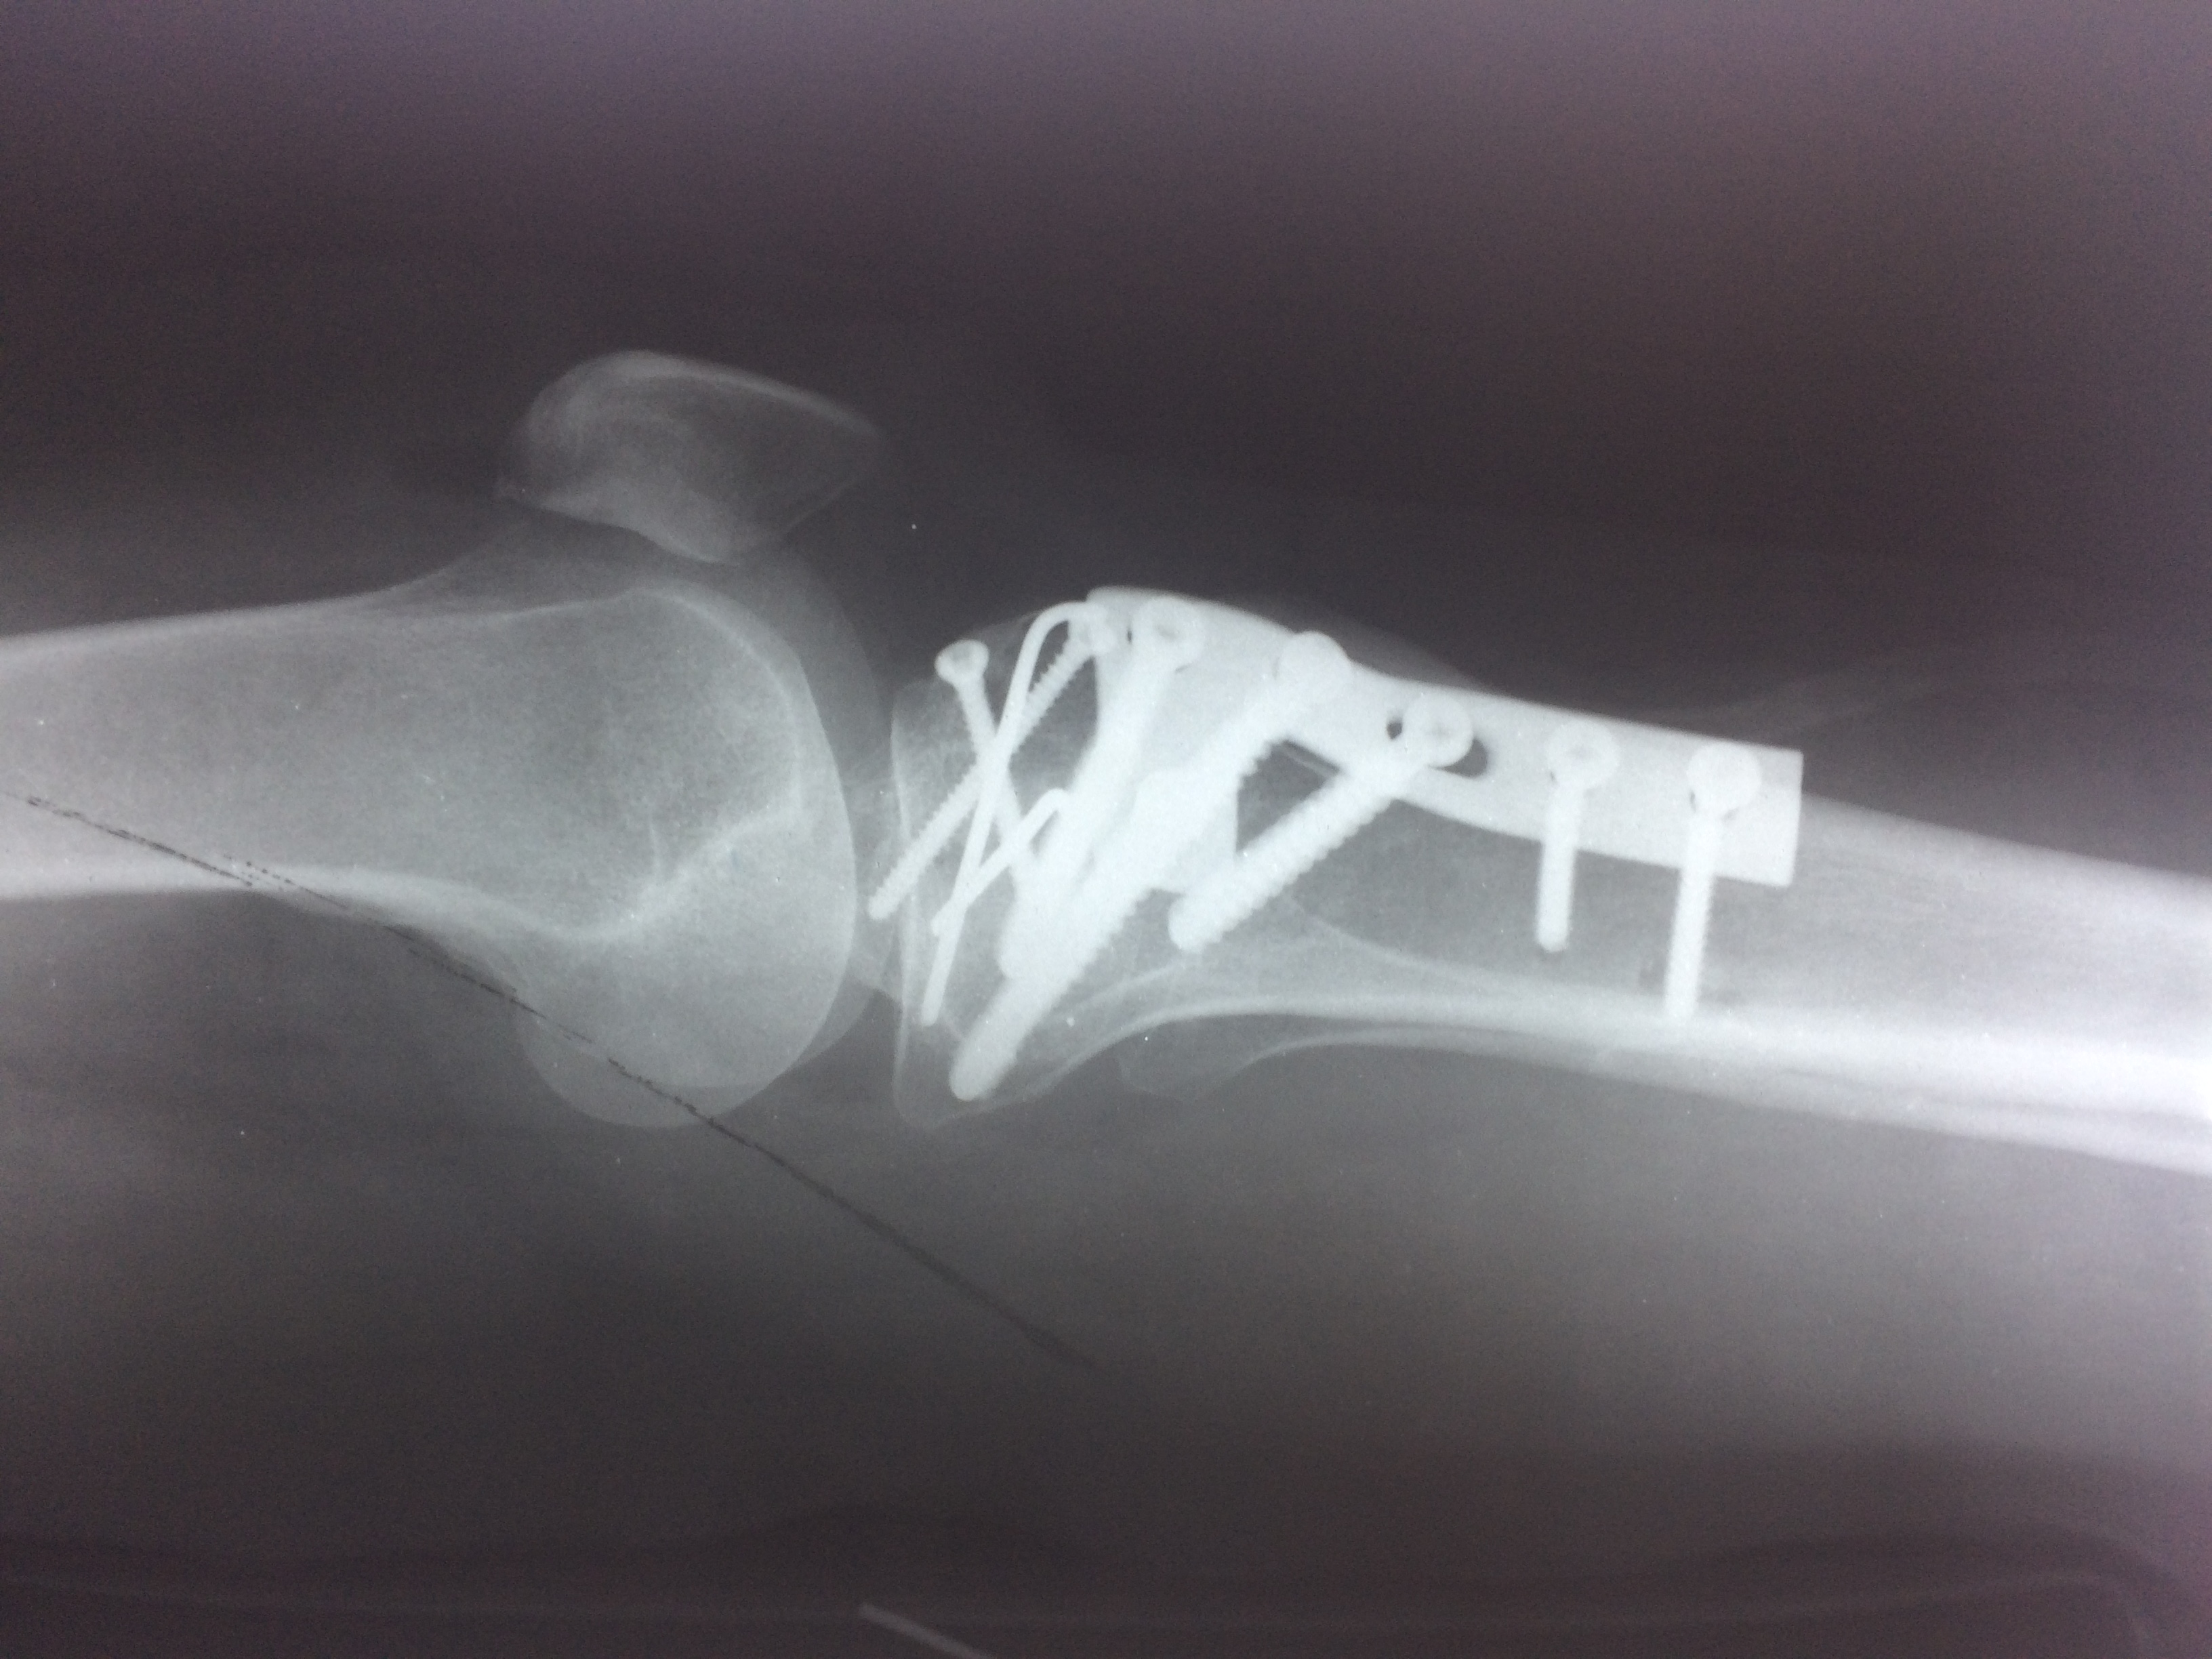

Операция - открытая репозиция, остеосинтез большеберцовой кости опорной пластиной с костной ксенопластикой маетриалом "Остеоматрикс". На контрольных снимках в три и шесть месяцев имеется консолидация перелома, миграции фиксатора нет, имеется остеоинтеграция ксенопластического материала. Функция коленного сустава полная.

Отдаленные результаты через 6 (шесть) месяцев